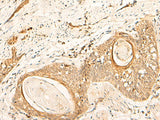

Applications IHC

IHC  1:40-1:200